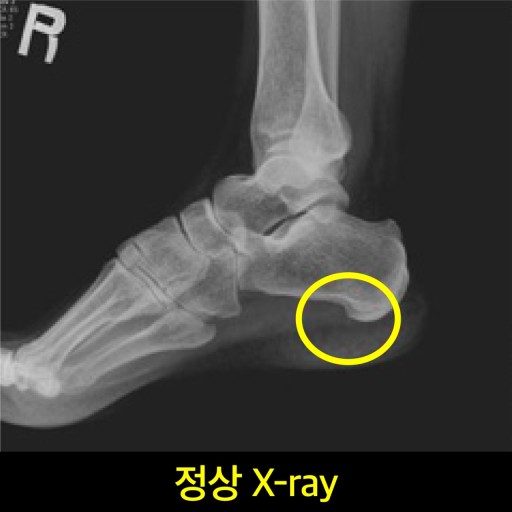

족저근막염은 발바닥을 지지해주는 근막에 염증이 생긴 상태로,

족저 근막염 증상 2. 뒤꿈치 통증

통증 부위는 대부분 발뒤꿈치 안쪽 또는 중앙 부위예요.